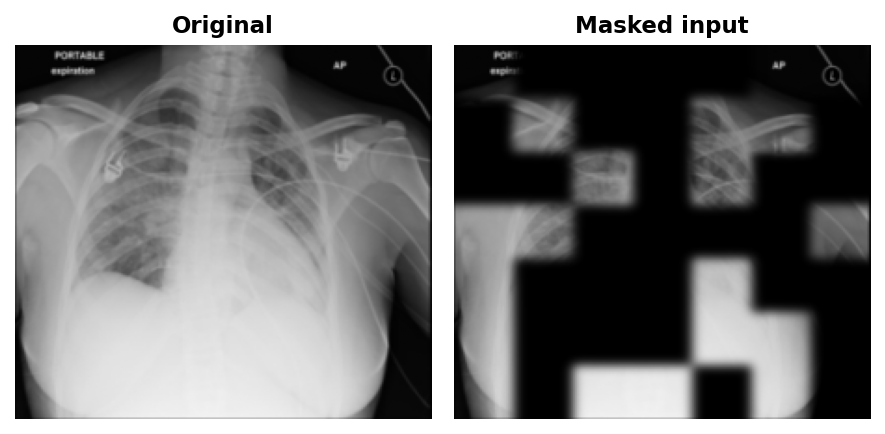

1. Masking. Before the first convolution, the 224x224 input is divided into non-overlapping 32x32 patches. 60% are randomly selected and zeroed out in raw pixel space. This is the key architectural difference from MAE: a ViT only processes tokens for visible patches, so masked content never enters the computation at all. A CNN has no such luxury: convolutional kernels slide over the entire image regardless. Masking in pixel space before the first convolution is necessary, but it does not prevent leakage on its own. The paper's solution is sparse convolutions that physically skip masked positions entirely.

Fix 1: Input-level masking instead of per-stage sparse simulation. The original SparK simulates sparse convolution using standard PyTorch operators: after each residual stage, it re-applies a downsampled version of the mask to the feature map, zeroing masked positions before the next stage sees them. This prevents masked-region values from accumulating across layers. This implementation takes the simpler route: zero masked patches once at input and run standard Conv2d through all four stages. The leakage cost is real but bounded, and on 112k images rather than ImageNet's 1.28M the easier pretext task is the right call.

return imgs * (1.0 - mask_px), mask_px With sparse convolutions, feature maps are zero at every masked position: the decoder must reconstruct from the 7×7 bottleneck alone. With standard convolutions, the kernel still slides over zeroed patches, so visible neighbours bleed through: the decoder gets a free spatial hint at every masked boundary before reconstruction runs. This means the task is slightly easier than true SparK. On 112k images rather than ImageNet's 1.28M, that trade-off is acceptable; an easier pretext task is less likely to leave the encoder under-trained. That's also why I set the mask ratio to 60% rather than MAE's 75% to make the task easier.